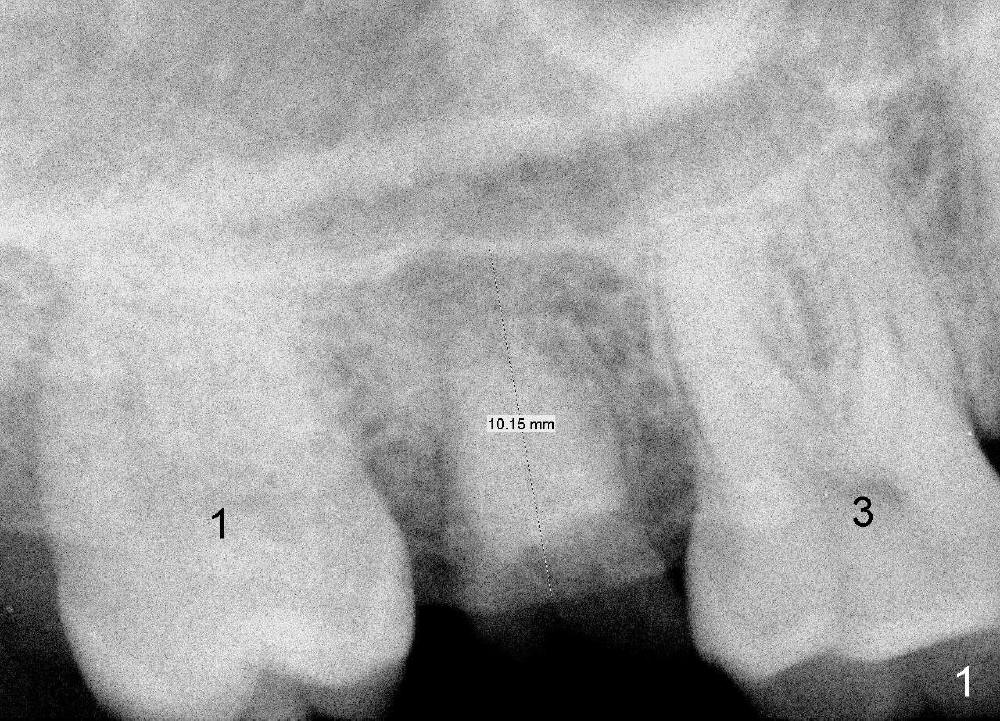

A 42-year-old man is afraid of dentistry. Residual roots of #2 remain untreated for at least 2.5 years (Fig.1). Both the mesiodistal space and the height are limited and unfavorable to restoration (Fig.2,3). Finally he agrees to have treatment, since the tooth #15 is worn so much that it is sensitive to mastication. When the tooth #2 is extracted, the socket is triangular without septum (Fig.4); the bottom of the socket is flat and easy for osteotomy. A 5x17 mm tap has obtained stability once it is placed ~ 14 mm deep (Fig.5). A 5x14 mm implant is placed with insertion torque > 60 Ncm (Fig.6 I), followed by placement of 4x3 mm abutment (A).